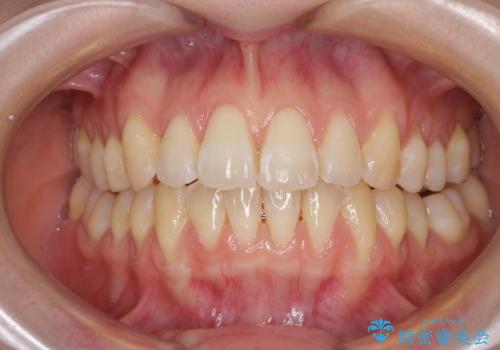

気になるデコボコとオープンバイト インビザラインでの矯正治療

- 前歯のデコボコと上下が開いていることを気にして来院された患者様です。

いわゆるオープンバイトは、インビザラインによる治療が適しているため、インビザラインにて治療を行うこととしました。